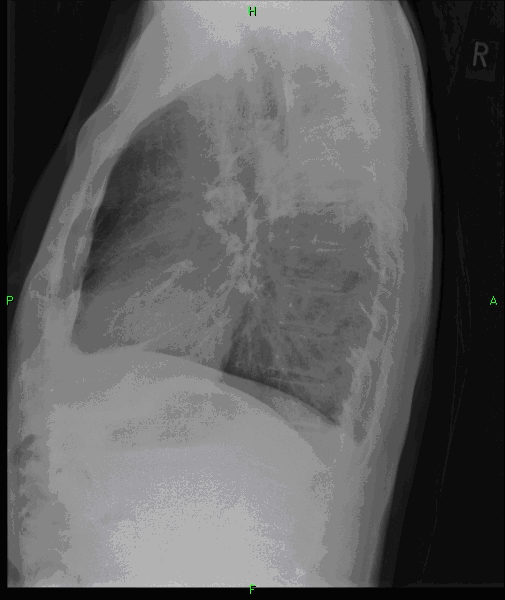

Unklare verdichtungen der lunge links. CAS Article PubMed Google Scholar. Die konventionelle Röntgenaufnahme der Lunge zeigte bipulmonale laterale Verschattungen verdächtig auf das Vorliegen einer atypischen Pneumonie Abb1. Neben der Lungenfunktionsprüfung werden zur Diagnose einer Lungenfibrose bildgebende Verfahren angewandt.

Differenzierung anhand der Wachstumsrate Die Wachstumsrate ist ein wichtiger Faktor für die Evaluation der Malignitätswahrscheinlichkeit bei unklaren pulmonalen Knoten. In Bauchlage wiederholt werden. Diagnostischer Standard ist eine Röntgenuntersuchung des Thorax in Kombination mit einer Computertomographie.

Lässt sich zwischen realen Verdichtungen und Belüftungsstörungen nicht unterscheiden muss die Untersuchung ggf. Definitionsgemäß ist es notwendig dass die Begrenzung so scharf ist dass eine Abmessung möglich ist. Verdichtung Röntgen Lunge.